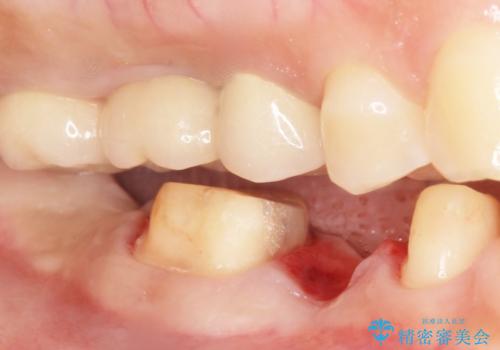

- 歯が折れてなくなってしまったことを主訴に来院された患者様です。

精査したところ、右下の奥歯2本(右下75)は大きなう蝕により歯冠が崩壊し保存不可能な状態でした。

保存不可能な歯を抜去し、オールセラミックのブリッジによる補綴治療を行いました。